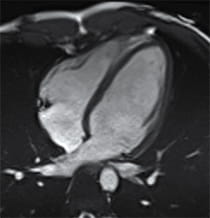

Image of LVNC Heart.

Image of a heart with left ventricular non-compaction cardiomyopathy.

What Is Left Ventricular Non-Compaction Cardiomyopathy (LVNC)?

In LVNC, muscle in the heart's left ventricle — one of two lower chambers — becomes sponge-like, with extra space between the muscle tissues. These heart muscle changes can affect how the left chamber pumps blood and can allow blood clots to form in the chamber.